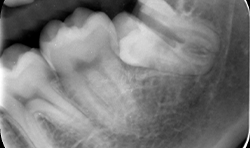

Different thin metallic blades may be connected to the Magnetic Max handpiece, sending a magnetic wave on the tip. The Magnetic Max imparted to blade a longitudinal movement along the central axis, moving up and down between root surface and lamina dura of the alveolus in a repetitive circumferential fashion, providing a driving mechanism of longitudinal movements. This movement also allows the maintenance of lamina dura for wisdom teeth (Figs. 4a-4c).

Fig. 4b

Fig. 4c